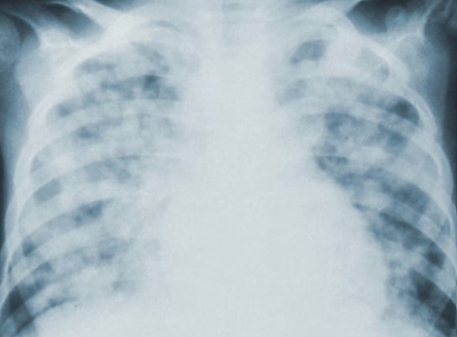

폐기흉은 폐에 구멍이 생겨 공기가 흉막강으로 유입되면서 폐가 정상적으로 기능하지 못하는 질환입니다. 초기에는 단순 통증으로 보일 수 있지만, 심각해지면 호흡부전으로 이어질 수 있어 조기 진단과 치료가 중요합니다.

폐기흉은 크게 자발성, 이차성, 외상성으로 구분됩니다. 특히 키가 크고 마른 체형의 젊은 남성, 흡연자에서 발생 위험이 높습니다. 자발성은 별다른 질환이 없는 상태에서 갑자기 나타나며, 이차성은 결핵이나 폐기종, 폐암 같은 기저 질환이 원인이 됩니다. 외상성은 교통사고, 수술, 시술 중 손상으로 발생합니다. 생활 습관과 기존 질환이 주요한 원인 요인으로 작용합니다.

폐기흉의 증상은 갑작스럽게 나타나며 빠른 대처가 필요합니다. 대표적으로 갑작스러운 흉통과 호흡곤란이 있으며, 심할 경우 청색증, 호흡부전, 심장 기능 저하까지 이어질 수 있습니다. 폐기흉 환자의 약 절반은 재발할 수 있어, 초기 증상 발생 시 지체 없이 의료진의 진단을 받는 것이 중요합니다. 경미한 증상이라도 무시하지 않고 빠른 대응이 필요합니다.